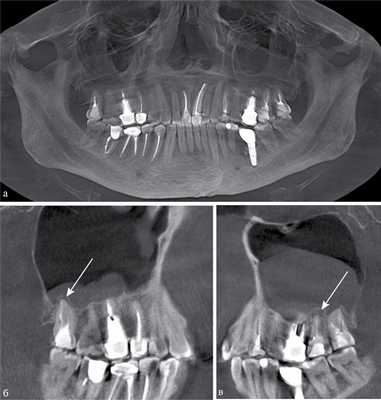

Рис. 1. КЛКТ. Панорамная (а) и мультипланарные реконструкции правого (б) и левого (в) верхнечелюстных синусов пациента М., 37 лет. Диагноз: двусторонний одонтогенный хронический верхнечелюсной синусит. Отмечаются КТ-признаки хронического гранулематозного периодонтита зубов 1.8, 2.7, 2.8 (в виде очагов деструкции у верхушек корней, округлой формы, с четкими ровными контурами). Нижние костные стенки синусов истончены, не прослеживаются в области периодонта зубов 1.8 и 2.8 (указаны стрелками). В нижнем отделе правого верхнечелюстного синуса определяется пристеночное мягкотканное образование гомогенной структуры с полицикличным верхним контуром. Левый верхнечелюстной синус субтотально заполнен мягкотканным содержимым гомогенной структуры с округлым верхним контуром.